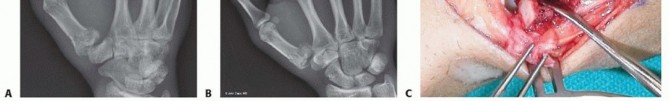

Closed Reduction and Percutaneous Pinning (CRPP)

CRPP is the treatment of choice for classic Bennett fractures where the volar-ulnar fragment is too small to reliably accept a lag screw, yet the joint can be anatomically reduced closed. The reduction maneuver is highly specific, designed to counteract the deforming forces of the APL and Adductor Pollicis. Longitudinal traction is applied to the thumb, followed by palmar abduction and pronation. Direct pressure is then applied to the dorsal-radial aspect of the metacarpal base, effectively pushing the shaft back into the anatomic cradle of the intact volar-ulnar fragment.

Once anatomic reduction is confirmed via multi-planar fluoroscopy, percutaneous fixation is achieved. Typically, two 0.045-inch or 0.062-inch Kirschner wires are utilized. The first wire is driven from the dorsal-radial aspect of the metacarpal shaft directly into the trapezium, effectively neutralizing the proximal pull of the APL. A second wire is often placed transversely from the first metacarpal shaft into the second metacarpal to control rotation and maintain the web space. Pins are cut outside the skin and capped to facilitate easy removal in the clinic.

Image

Open Reduction and Internal Fixation (ORIF) - Wagner Approach

For fractures with large volar-ulnar fragments (>20% of the articular surface), displaced Rolando fractures, or cases where closed reduction fails, ORIF is unequivocally mandated. The classic Wagner approach provides unparalleled exposure to the thumb CMC joint. A curvilinear incision is made along the glabrous border of the thenar eminence, curving dorsally at the level of the CMC joint.

Meticulous superficial dissection is required to identify and protect the sensory branches of the superficial radial nerve dorsally and the palmar cutaneous branch of the median nerve volarly. The thenar musculature (abductor pollicis brevis and opponens pollicis) is sharply elevated from the metacarpal shaft and retracted volarly. The joint capsule is then incised longitudinally or in an L-shaped fashion to expose the articular surface. The hematoma is evacuated, and the fracture fragments are meticulously debrided of interposed soft tissue.

For a large fragment Bennett fracture, the shaft is reduced to the volar-ulnar fragment using a pointed reduction clamp. Provisional fixation is achieved with a K-wire. A 1.5mm or 2.0mm lag screw is then placed perpendicular to the fracture plane. The near cortex must be overdrilled (gliding hole) and the far cortex underdrilled (thread hole) to achieve true interfragmentary compression. The screw head should be countersunk to prevent hardware prominence beneath the thenar muscles.